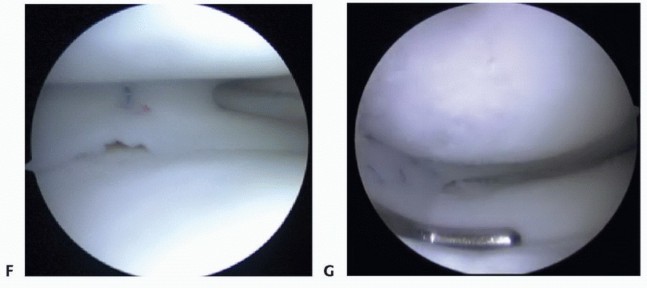

TECH FIG 5 • Medial meniscus technique. A. Medial approach. B. Notchplasty performed under PCL. C,D. Guide pin placement into the posterior horn insertion. E. Shuttle suture through the posterior tunnel exiting the medial portal. F. Anterior arthrotomy incorporating medial portal. 5. ## Delivery and Fixation of Medial Meniscus

Via a shuttle suture, deliver the posterior bone plug suture through the notch and down the posterior tunnel, exiting anteriorly. Also, deliver the posterior passing suture through the arthrotomy and out of the posteromedial capsule to assist in passing the allograft. Via the parapatellar arthrotomy, deliver the meniscal allograft into the knee and fully seat the posterior bone plug into the posterior tunnel (

TECH FIG 6A-C

). A hemostat or probe can be used to aid in the delivery of the plug under the PCL. Applying a valgus stress to the knee while pulling on the posterior bone plug sutures through the tibial tunnel and the posterior passing suture helps to reduce the posterior horn. Similar to reducing a bucket-handle tear, a blunt trocar or probe may assist in reducing the meniscus under the femoral condyle (

TECH FIG 6D

).

Using zone-specific cannulas, secure the allograft to the periphery using an inside-out technique going from posterior to anterior (

TECH FIG 6E

). This will secure the posterior two-thirds of the graft to the capsule.

Through the parapatellar arthrotomy, determine the anterior horn insertion site and place a Beath guide pin in its center. This should typically be located at the same location as the recipient's anterior horn insertion. However, sometimes, the transplant's anterior insertion site needs to be slightly modified to let it seat appropriately (where it wants to insert once sutured at the posterior horn and body).

Drill a blind 9-to 10-mm tunnel vertically to a depth sufficient to accept the anterior allograft bone plug (

TECH FIG 6F

Drill a 2-mm hole perpendicular to the tunnel from the anterior tibial cortex to enter the tunnel base. Place a shuttle stitch through the 2-mm hole and exit up the anterior tunnel.

Shuttle-exchange the shuttle stitch and the anterior bone plug suture. Deliver and fully seat the anterior

bone plug in the tunnel (

TECH FIG 6G

Tie the bone plug sutures over the bone bridge rather than tying the sutures over a plastic ligament button (

TECH FIG 6H

Complete the meniscal repair to the anterior capsule using an open repair technique (

TECH FIG 6I,J

TECH FIG 6 • A,B. Medial meniscus delivery. Shuttle suture and delivery of the posterior bone plug and meniscus. C. Meniscus delivered into joint prior to reduction under condyle. D. Meniscus following reduction. E. Inside-out suture placement (posterior to anterior). F. Anterior recipient tunnel created by reaming over guide pin. G. Anterior bone plug seated into tunnel. H. Bone plug sutures tied over anterior bone bridge.

(continued)

TECH FIG 6 •

I. Schematic of bone plug and meniscus fixation. J. Arthroscopic view of final graft in position. 6. ## Medial Meniscus Transplant Combined with Revision Anterior Cruciate Ligament Reconstruction